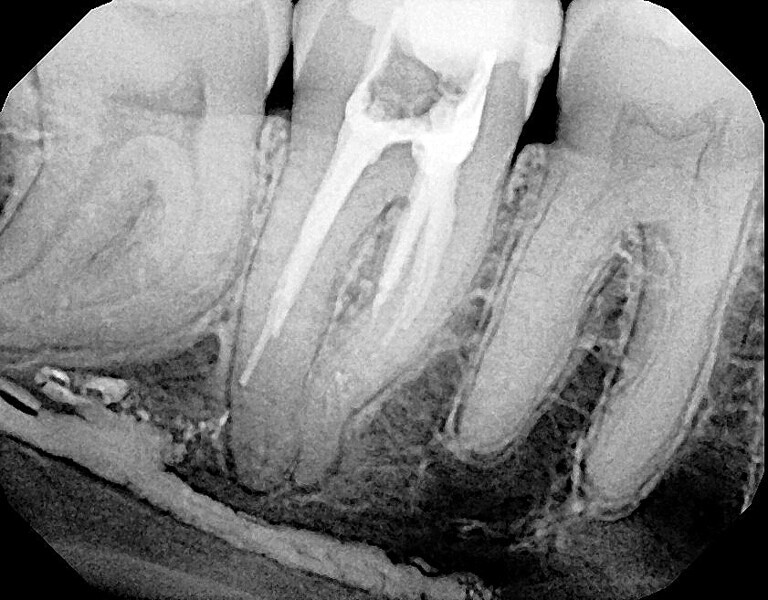

Fig. 14a: Case treated with Bassi Logic controlled memory nickel titanium files. Note the visualization of the third root on this lower molar and conservative canal preparation shape. (Courtesy of Dr. Alex Chan)

Fig. 14b: Case treated with Bassi Logic controlled memory nickel titanium files. Note the visualization of the third root on this lower molar and conservative canal preparation shape. (Courtesy of Dr. Alex Chan)